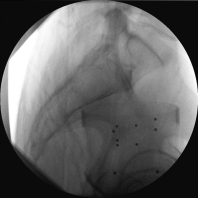

图像采集,医生在术中用床旁C型臂为患者手术部位拍摄X线影像资料。

STEP02

图像传输,机器人的“大脑”接收影像资料,并显示在屏幕上。